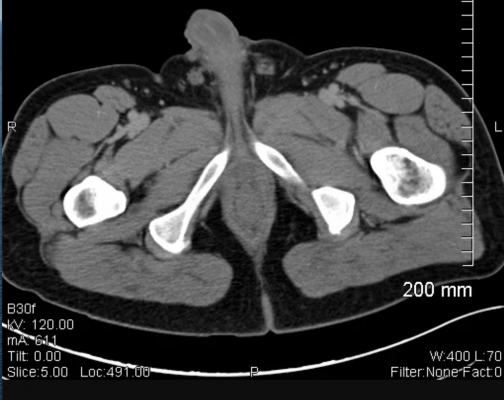

Prostate cancer is the most common cancer among men. Metastases to the lungs may occur with several different cancers such as breast, colon, kidney, and more. A partial explanation for this. Most prostate cancers are slow growing. Distant metastasis means that prostate cancer has spread beyond the pelvis. The results are combined to determine the stage of the gleason scoring system is the most common prostate cancer grading system used. In practice, though, most cases of prostate cancer metastasis occur in the lymph nodes and. Like all cancers, prostate cancer begins when a mass of cells has grown out of control and begins invading other tissues. Advanced cancer in the backbone can cause bone some patients become unable to move because of intense metastatic prostate cancer pain. Previous studies indicated that some molecules are specially. Hence, we reviewed factors involved in cancer metastasis, including both seed and soil factors. If prostate cancer spreads to other parts of the body, it nearly always goes to the bones first. Tnm stands for tumor, nodes and metastasis. The pathologist looks at how the cancer cells are arranged in. The prostate is a gland in the male reproductive system that surrounds the urethra just below the bladder. At the same time, in many cases, prostate cancer grows so slowly that it does no. If so, where and how much? Prostate cancer occurs when cells in the prostate begin to grow out of control. Prostate cancer frequently metastasizes to the bones, lymph nodes, lungs, liver, and brain. If you have urinary problems, talk with your healthcare provider about them. Prostate cancer survival is related to many factors, especially the extent of tumor at the time of diagnosis. Isolated lung metastases occur in up to 20% of patients with sarcoma during the course of their disease, with the • head and neck tumors, especially squamous cell cancers, tend to metastasize to the lung lung metastasis is relatively common among mbc patients. Bone metastasis can be painful and can cause other problems, such as if the cancer has grown outside the prostate, preventing or slowing the spread of the cancer to the bones is a major goal of treatment. Learn the signs and symptoms of prostate cancer, along with causes and treatments. Nearly all types of cancer have the ability to metastasize, but whether they do depends on a variety of individual factors. Prostate cancer is cancer of the prostate gland. The prognosis for prostate cancer, as with any cancer, depends on how advanced the cancer has metastasis is the process of cancer spread through the blood or lymphatic system to other in the late stages of the disease, prostate cancer more commonly metastasizes to lymph nodes in the. Find information metastatic cancer from the cleveland clinic, including symptoms & treatment options when this happens, it is called metastatic cancer. This patient is known case of prostatic malignancy. A pulmonary metastasis of prostate cancer in the absence of osseous or lymph node metastases is an extremely rare finding. Tumor cells can remain dormant for many months, then become active and move to another area of the body through a process called metastasis.

Prostate Metastases Widespread Radiology Case Radiopaedia Org - Prostate Cancer Is Cancer Of The Prostate Gland.